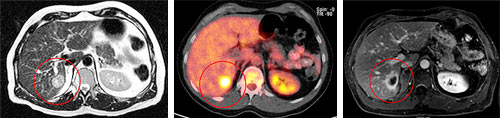

Dieses Behandlungsbeispiel zeigt den Behandlungsverlauf einer 46-jährigen Patientin mit bekannter Brustkrebserkrankung. Sie entwickelte eine lebensbedrohliche Symptomatik mit einem beginnenden Querschnittsyndrom. Die bildgebende Untersuchung der Halswirbelsäule konnte eine Metastase im oberen Teil des Rückenmarks nachweisen (linkes Bild). Es drohte eine unmittelbare Lähmung der Arme und Beine. Die Patientin wurde in unser Cyberknife Zentrum überwiesen und in einer einmaligen, 1-stündigen Sitzung behandelt.

4 Wochen nach der Behandlung war die Metastase nicht mehr nachweisbar (rechtes Bild). Die Patientin hatte eine gute Lebensqualität und konnte die Praxis wieder zu Fuß verlassen.